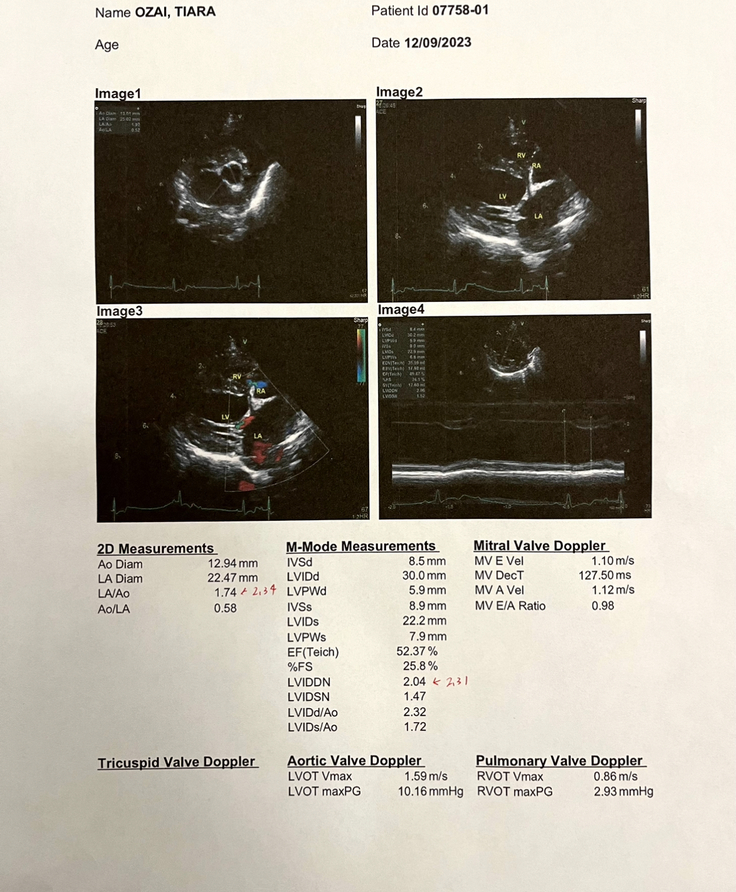

現状、僧帽弁、三尖弁共に

軽度の逆流はあるとの事なので